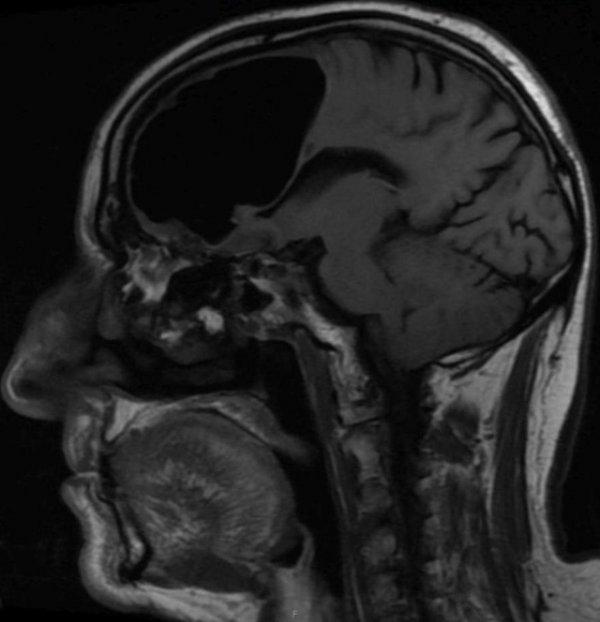

Doktorlar röntgene baktığında beynin sağ tarafında 9 santimlik siyah bir görüntü gördü. Doktorlar, 84 yaşındaki hastanın sağ ön lobunun olmadığını fark etti.

Doktorlar hastanın pnömatosel rahatsızlığı ( akciğerde kistik hava boşluğu) olduğu için beyin dokusuna zarar verdiği görüşünde birleşti.